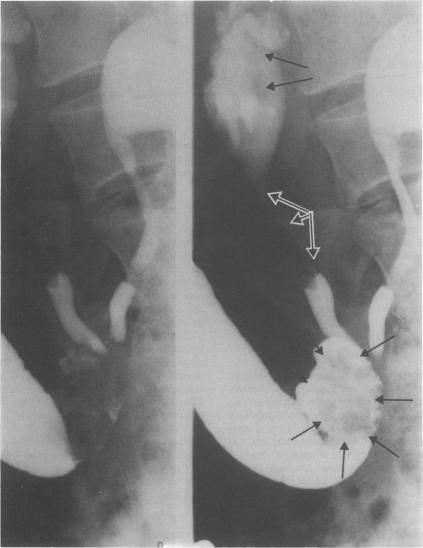

Following cystectomy for transitional cell carcinoma a 63 year old woman developed recurrent tumours in the upper urinary tract and ileal conduit, suggesting that malignant transitional cells can auto-implant in ileal epithelium. This phenomenon has not been previously reported. We illustrate the value of retrograde urogram via an ileal conduit following cystectomy for cancer.